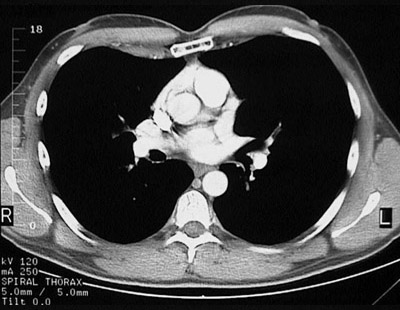

[T7] This is a normal chest CT scan demonstrating the right lung and left lung and pectoralis major muscle and right atrium and pulmonic trunk and right pulmonary artery and left pulmonary artery and left atrium and aortic root and sternum and descending aorta and azygous vein and esophagus and latissimus dorsi muscle and subscapularis muscle and spine of scapula and infraspinatus muscle and rhomboid major muscle and trapezius muscle and sacrospinalis muscle in the upper chest.